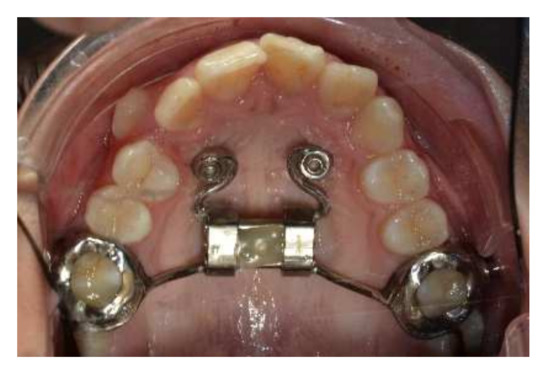

Figure 4.

Herbst appliance reinforced with an Hybrid Hyrax Expander and two miniscrews in the lower arch.

To achieve the treatment objectives, a hybrid palatal expander was initially applied, anchored to two palatal miniscrews and to first upper molars bands, to prepare the arch in a transverse direction. The patient’s parents gave their informed consent for the treatment. Having obtained an adequate size of the upper arch in a sagittal and transverse direction, the Herbst appliance was applied and anchored superiorly to the hybrid palatal expander to allow mandibular advancement and at the same time avoid excessive retroclination of the upper incisors and distalization of the upper molars, which could lead to an excessive increase in the nasolabial angle during Herbst therapy (Figure 4 and Figure 5).

After 20 activations, the Hybrid Hyrax Expander was stabilized and maintained in situ for the next 6 months to promote suture ossification. At this time, it was bonded to the Herbst device. The lower teeth from canine to canine were solidarized with a buccal retainer. Two miniscrews were inserted between the first and second lower premolars and connected with a power chain to the lower canines to avoid lower incisors proclination.

The Herbst device was reinforced by TADs. In the upper arch, two palatal TADs were inserted both to improve skeletal expansion and to avoid molar distalization during jaw advancement. In the lower arch, two TADs were inserted between the first and second premolar and connected to canines with a power chain to avoid lower incisors proclination. Elements from 3.3 to 4.3 were solidarized with steel wire.